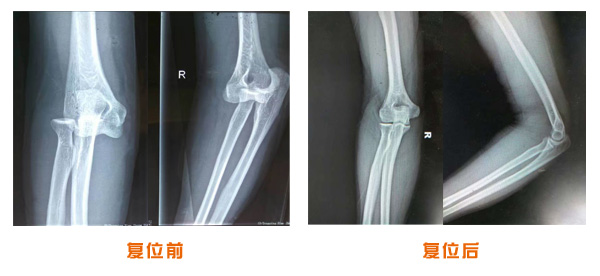

肘關(guān)節(jié)脫位骨折治療前后對(duì)比